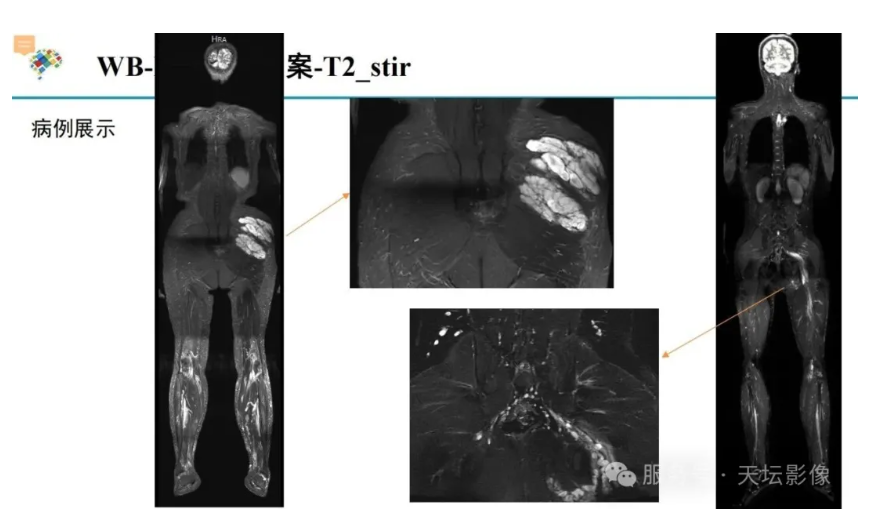

NF1相关丛状神经纤维瘤推荐MR扫描方案